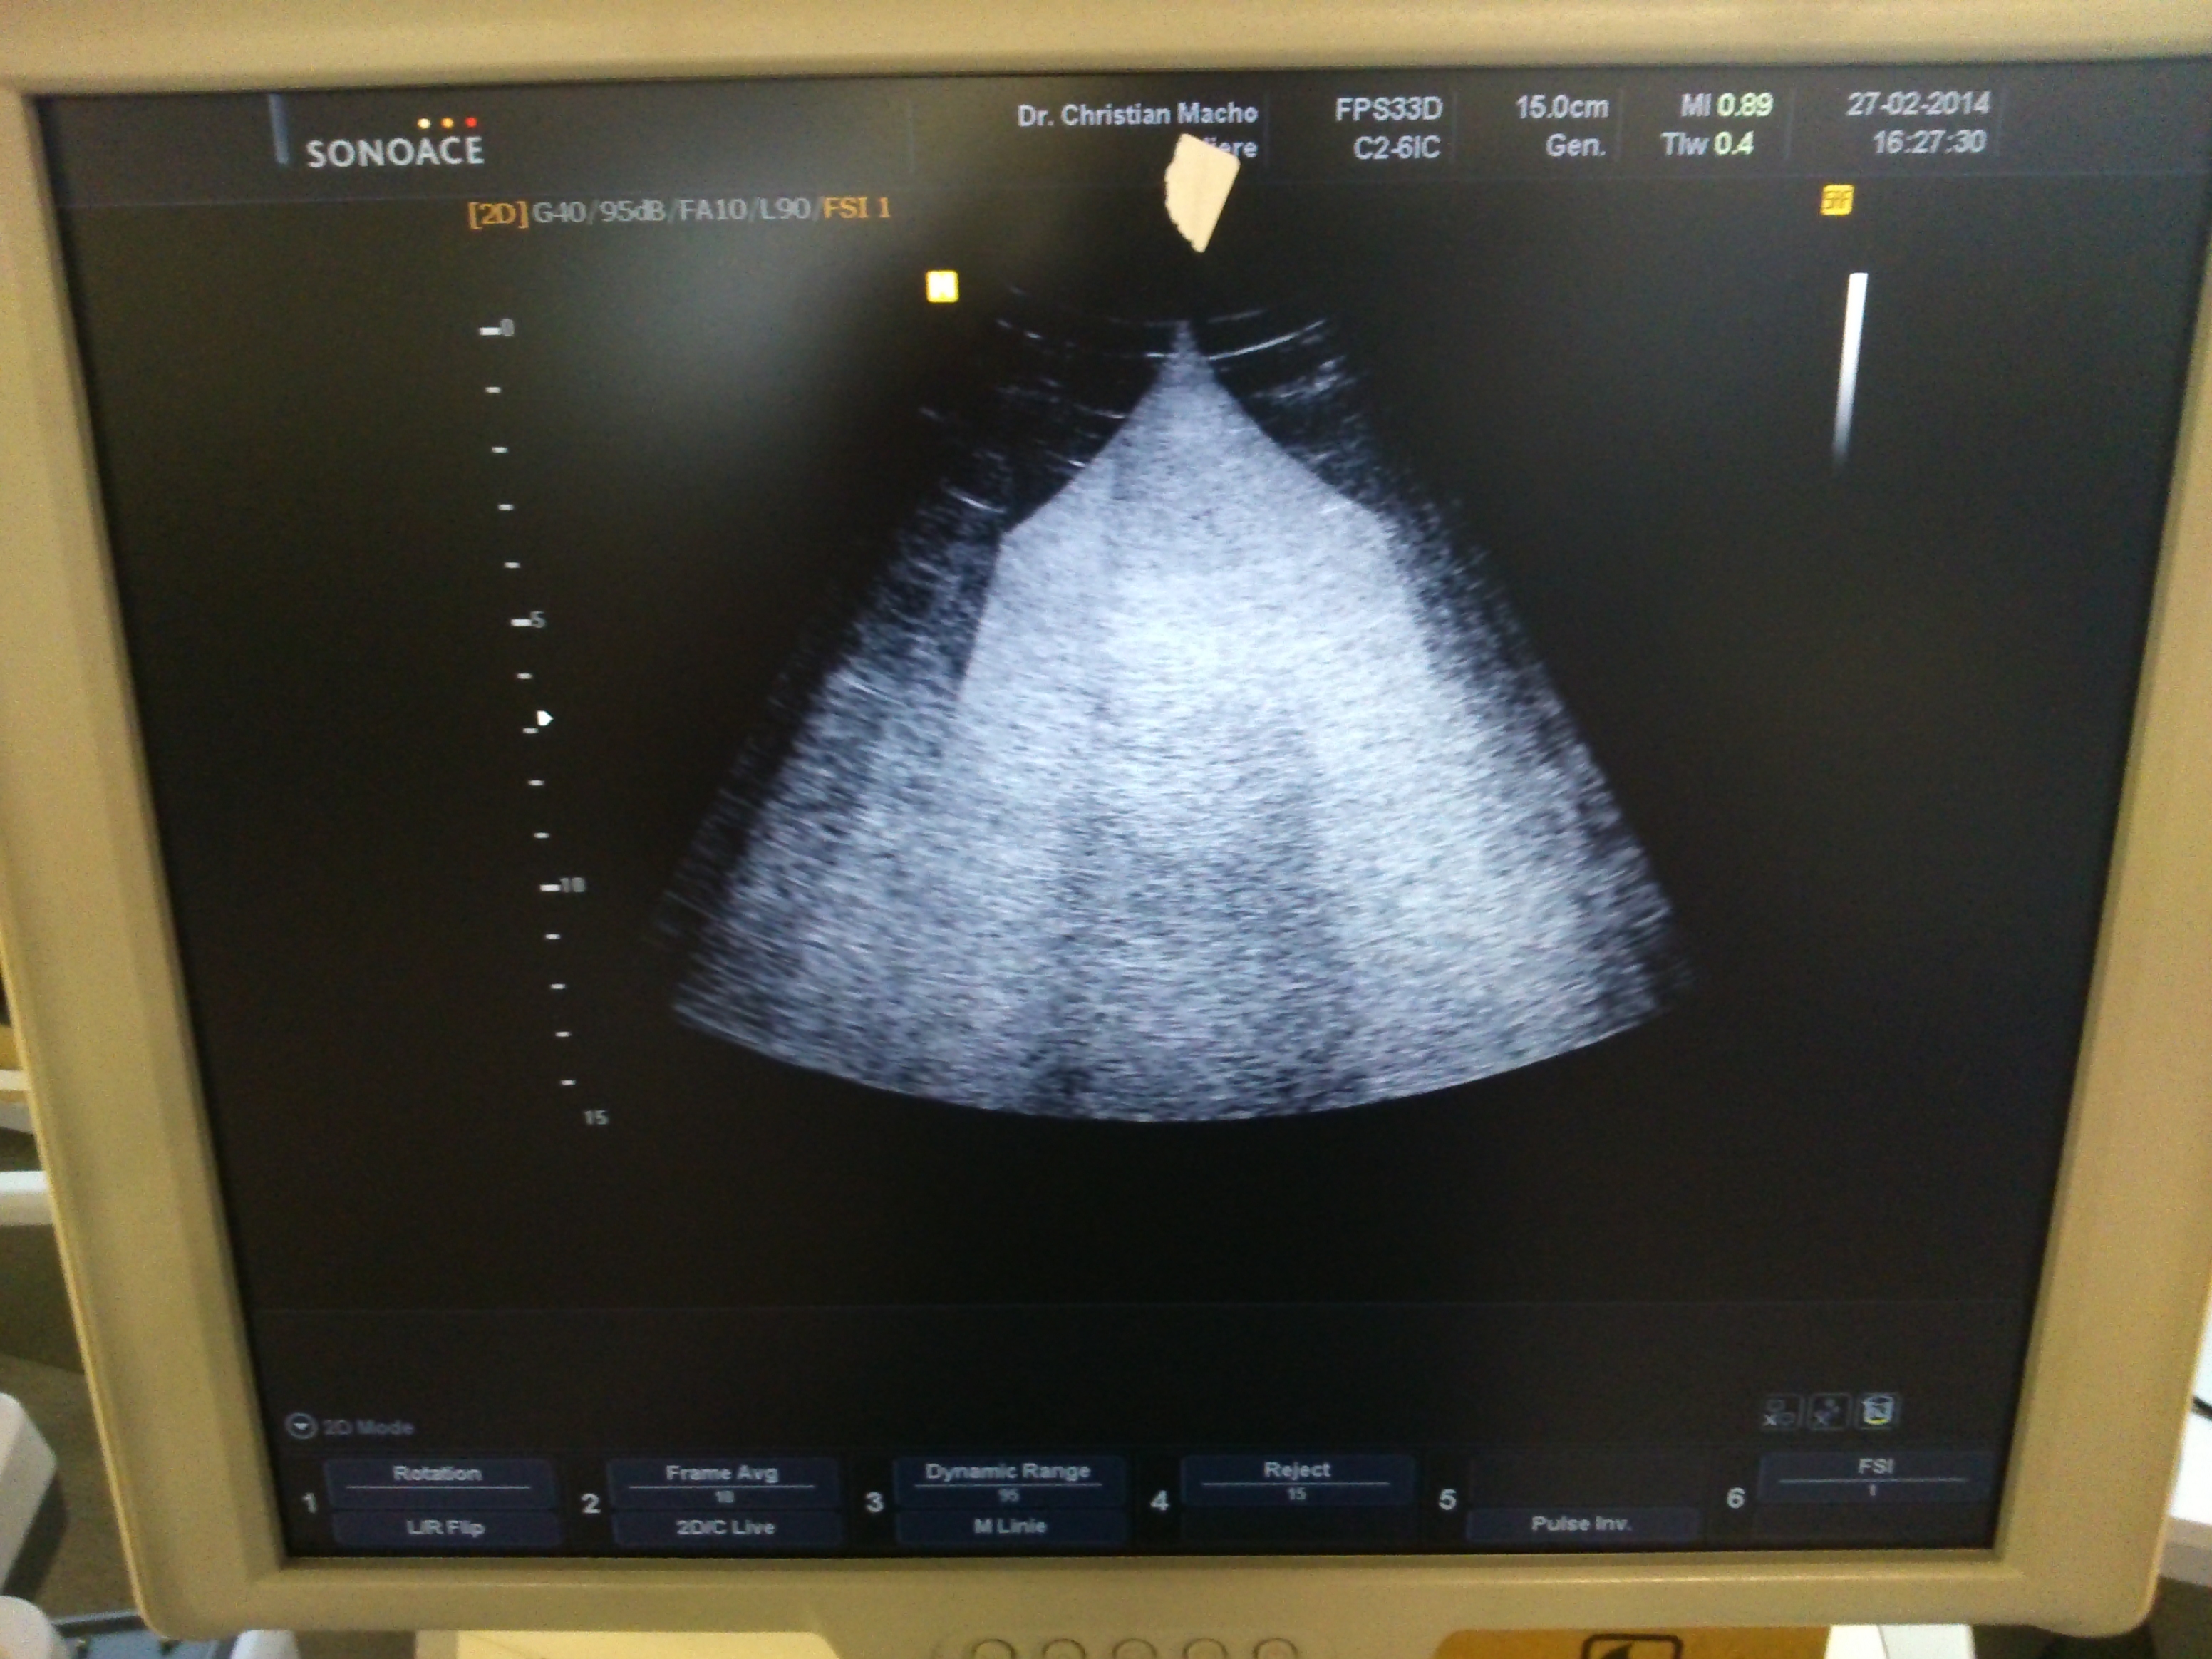

i have image problems with a beamforming board.

Does anyone have an idea why i get this horrible image at the screen?

it was helpful to know what happened at the beamforming board

it its a medison accuvix V10

the P/N is bd-348-bf 0A